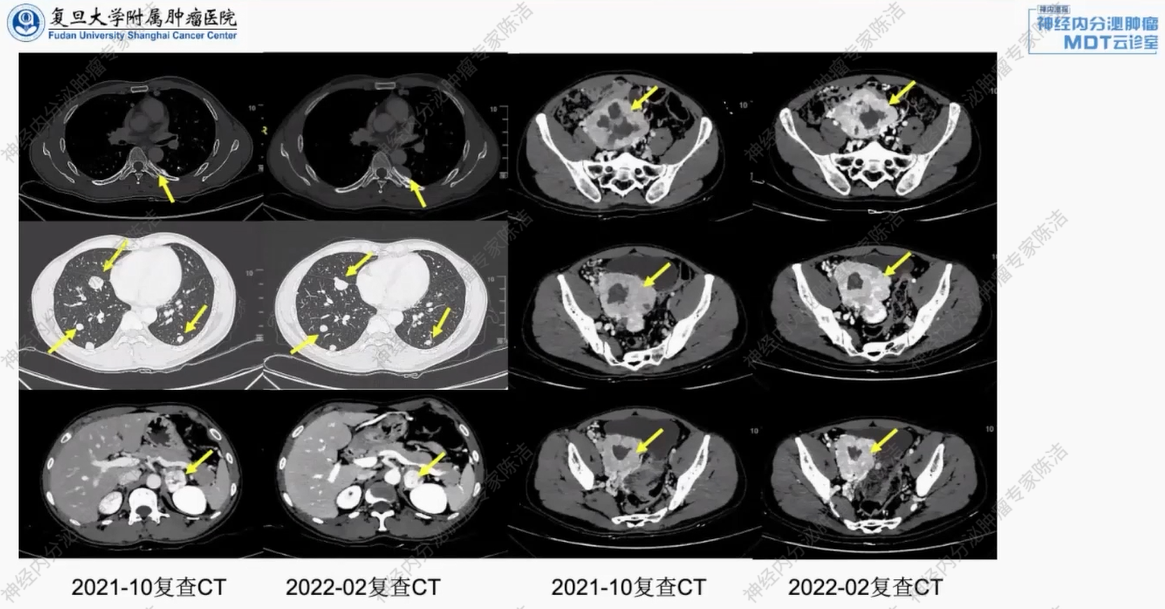

2021年10月复查增强CT,疗效评估为疾病稳定(SD)。继续原方案化疗。

2022年2月再次复查增强CT,疗效评估仍为SD。患者目前仍在此方案维持治疗中。

放射诊断科汤伟教授:MRI影像证实左侧肾上腺病灶富血供,符合嗜铬细胞瘤或转移瘤的影像学特征。复查的CT随访评估显示,在Captem化疗期间,无论是盆腔病灶、肾上腺病灶还是肺部转移灶,大小均无明显变化,总体疗效评估为SD。